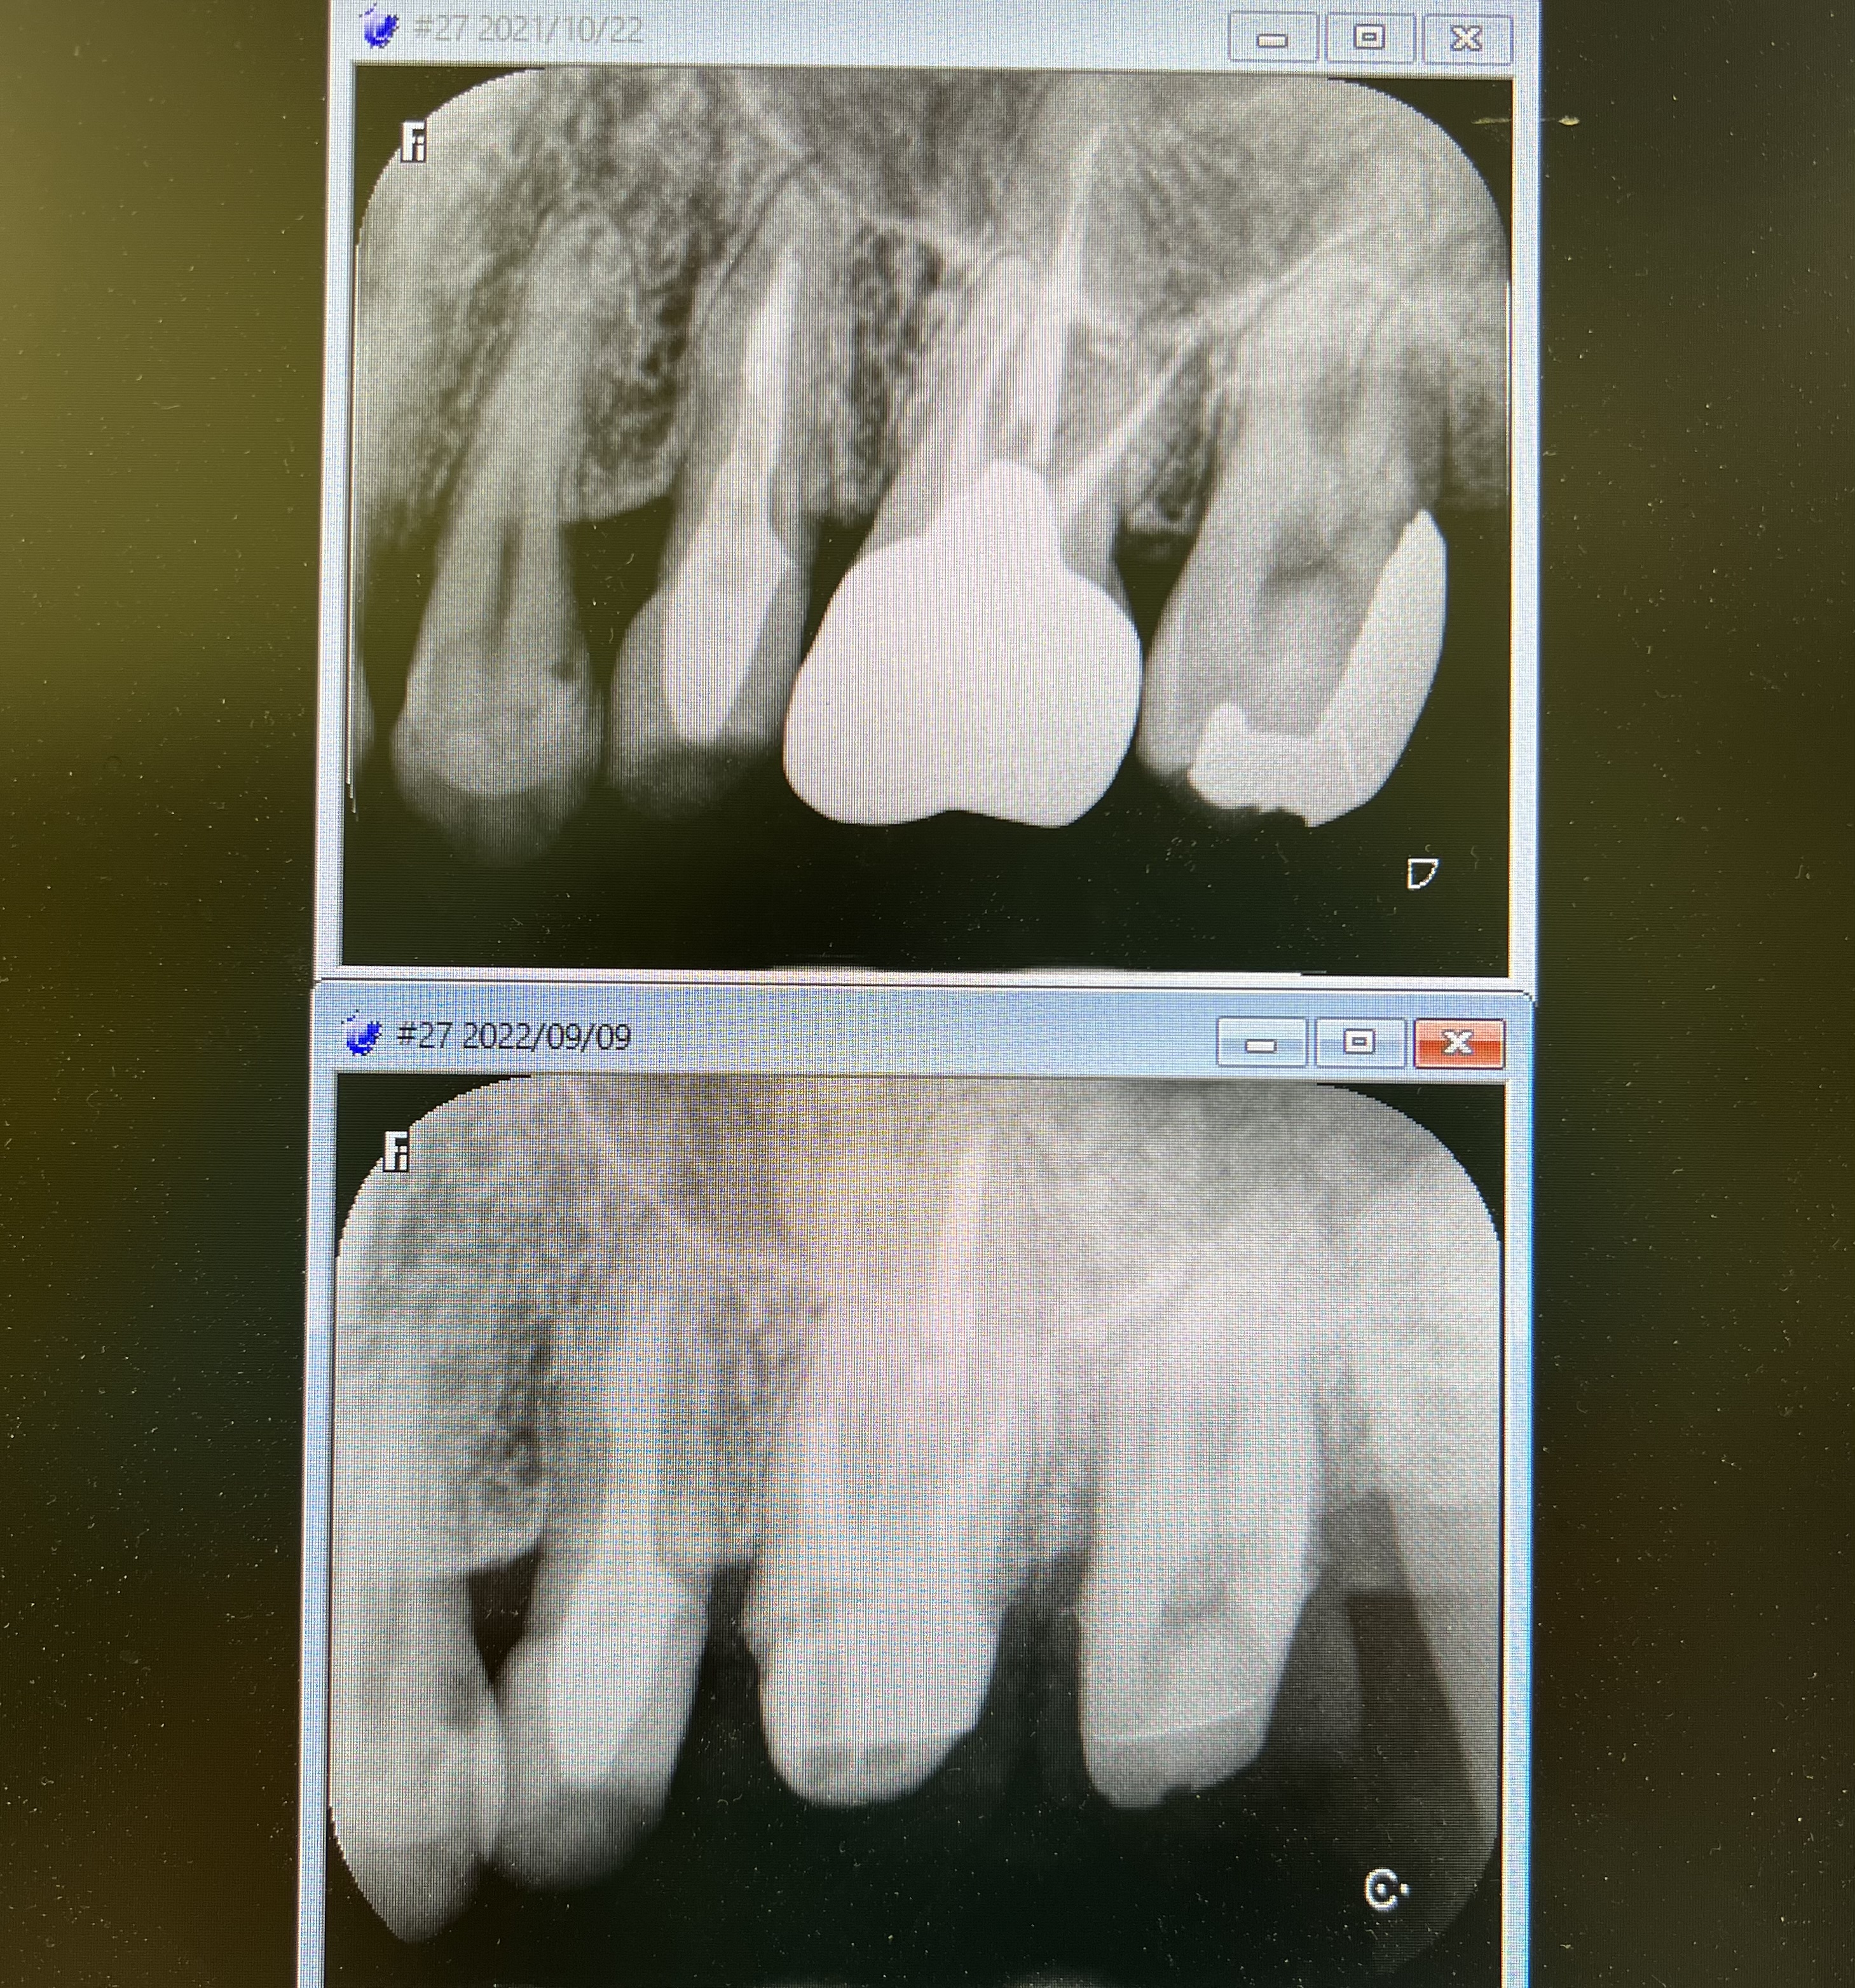

抜歯やインプラント回避して歯根保存してフルジルコニアクラウンを被せた症例

2023/04/11症例